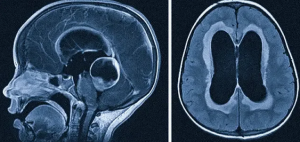

мографах с индукцией магнитного поля 1,5 и 3 Тл по стандартизированному протоколу исследования головного мозга с применением стандартных импульсных последовательностей в трех взаимно перпендикулярных плоскостях (Т1-, Т2-, TIRM), а также 3D Т1- MPRAGE (Magnetization Prepared Rapid Acquisition Gradient Echo) - Т1-импульсная последовательность градиентного эха с ускоренным сбором данных со следующими параметрами: время повторения (TR) 2000 мс, время эхо (ТЕ) 4,38 мс, угол отклонения (FA) 10°, FOV 250 мм, матрица 256 х 256, толщина среза 1 мм, количество срезов 160, время сканирования 11 мин. Для анализа структур головного мозга были использованы различные инструменты, доступные в программном обеспечении FreeSurfer версии 7.3.2 [23]. В автоматическом режиме была проведена МР-морфометрия с определением морфометрических показателей (объема в мм3, площади в мм2 и толщины в мм) для каждой структуры височных долей, представленной на рис. 1. Постпроцессинговая обработка состояла из нескольких последовательных этапов. Подготовительный этап включал линейное преобразование Талайраха, нормализацию интенсивности, удаление черепа и внемозговых тканей с помощью поверхностной деформации, отделение мозжечка и ствола мозга от головного мозга и разделение левого и правого полушарий [23]. Для определения внутренних (серо-белых) и пиальных (серо-ликворных) поверхностей коры применялся алгоритм деформируемой поверхности [24]. Процесс обработки

Статистический анализ проводился с использованием программного обеспечения Jamovi 2.3.28 и Microsoft Excel 2007 [28, 29]. Для анализа полученных результатов и выявления статистически значимых различий между группами были применены соответствующие методы статистического анализа. Количественные данные были описаны с использованием среднего значения и стандартного отклонения. При сравнении средних значений двух возрастных групп для количественных переменных использовался непараметрический U-критерий Манна-Уитни, что позволило учесть возможные выбросы и асимметрию в данных. Графическое изображение полученных результатов сегментации структур головного мозга с помощью программного пакета FreeSurfer показано на рис. 2 и рис. 4. Был проведен анализ линейной регрессии и определено процентное изменение средних значений для оценки трендов в изменении морфометрических показателей (объема в мм3, площади в мм2 и толщины в мм) структур височных долей. Для вычисления процентного изменения средних значений использовали формулу:

Общие изменения структур височных долей. Процентное изменение средних значений объема (мм3), площади поверхности (мм2) и толщины структур (мм) височных долей при сравнении исследуемых возрастных групп представлено в табл. 2, на рис. 2 и 3. Сегментация субполей гиппокампа и миндалевидного тела выполнялась с помощью отдельного анализа объемов этих структур. Процентное изменение средних значений объема (мм3) субполей гиппокампа и миндалевидного тела при сравнении исследуемых возрастных групп представлено в табл. 3 и на рис. 4.

Рис. 2. Значения объема, мм3 (слева), площади поверхности, мм2 (в центре) и толщины, мм (справа) структур височных долей для возрастных групп 0-7 лет (верхние столбцы) и 7-18 лет (нижние столбцы). Вертикальные линии обозначают медианы, левые и правые границы прямоугольников указывают на нижний и верхний квартили соответственно.

Fig. 2. Values of volume, mm3 (left), surface area, mm2 (middle), and thickness, mm (right) of temporal lobes structures for the age groups 0-7 years (upper columns) and 7-18 years (lower columns). Vertical lines indicate medians, while the left and right borders of the rectangles denote the lower and upper quartiles, respectively.